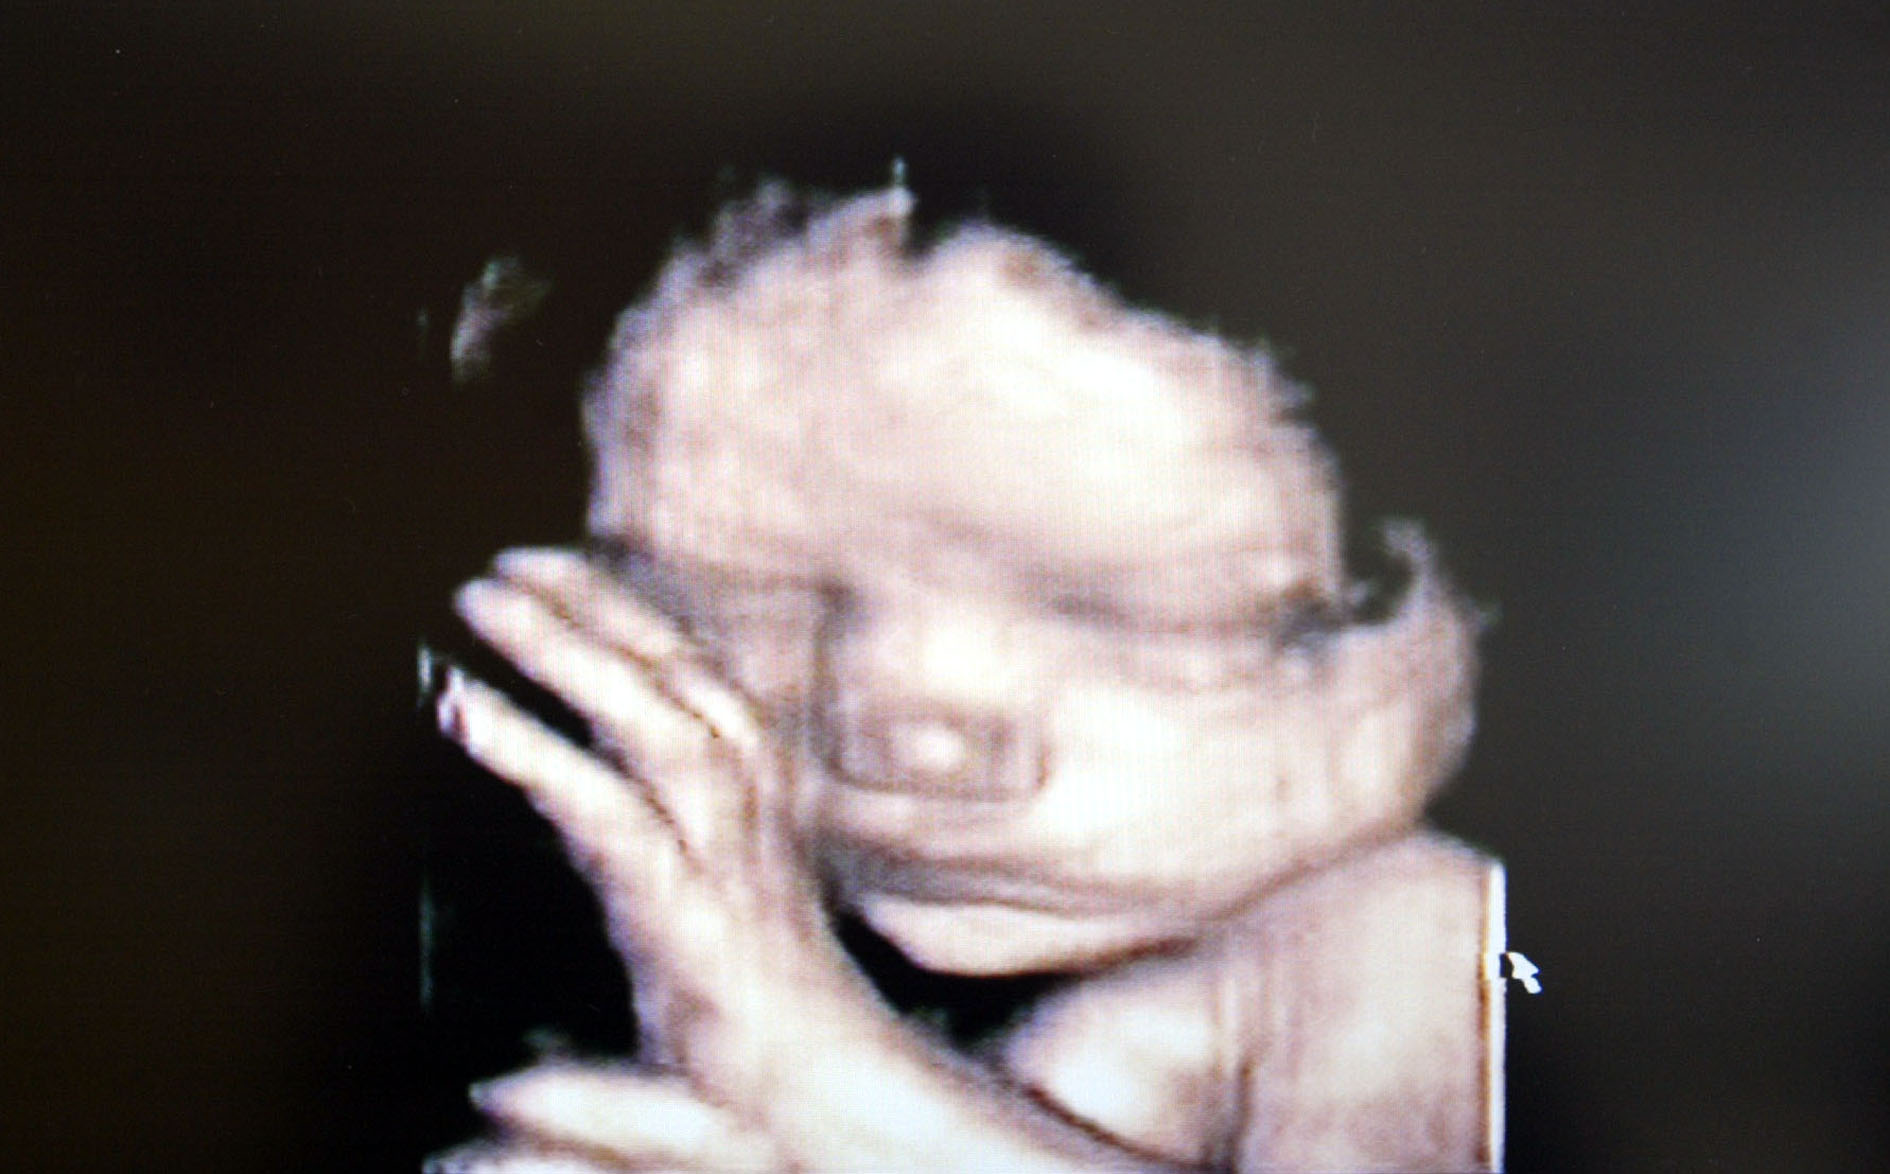

From www.pinterest.com

9 Months In The Womb A Remarkable Look At Fetal Development Through Can Water Hurt My Unborn Baby some pregnant women fear that too much water intake can lead to a drastic increase in the quantity of. Low amniotic fluid can cause labour. after your water breaks, how long the baby can survive depends on several different factors. Hydrocephalus, or “water on the brain,” is a condition associated with a buildup of cerebrospinal. does too. Can Water Hurt My Unborn Baby.